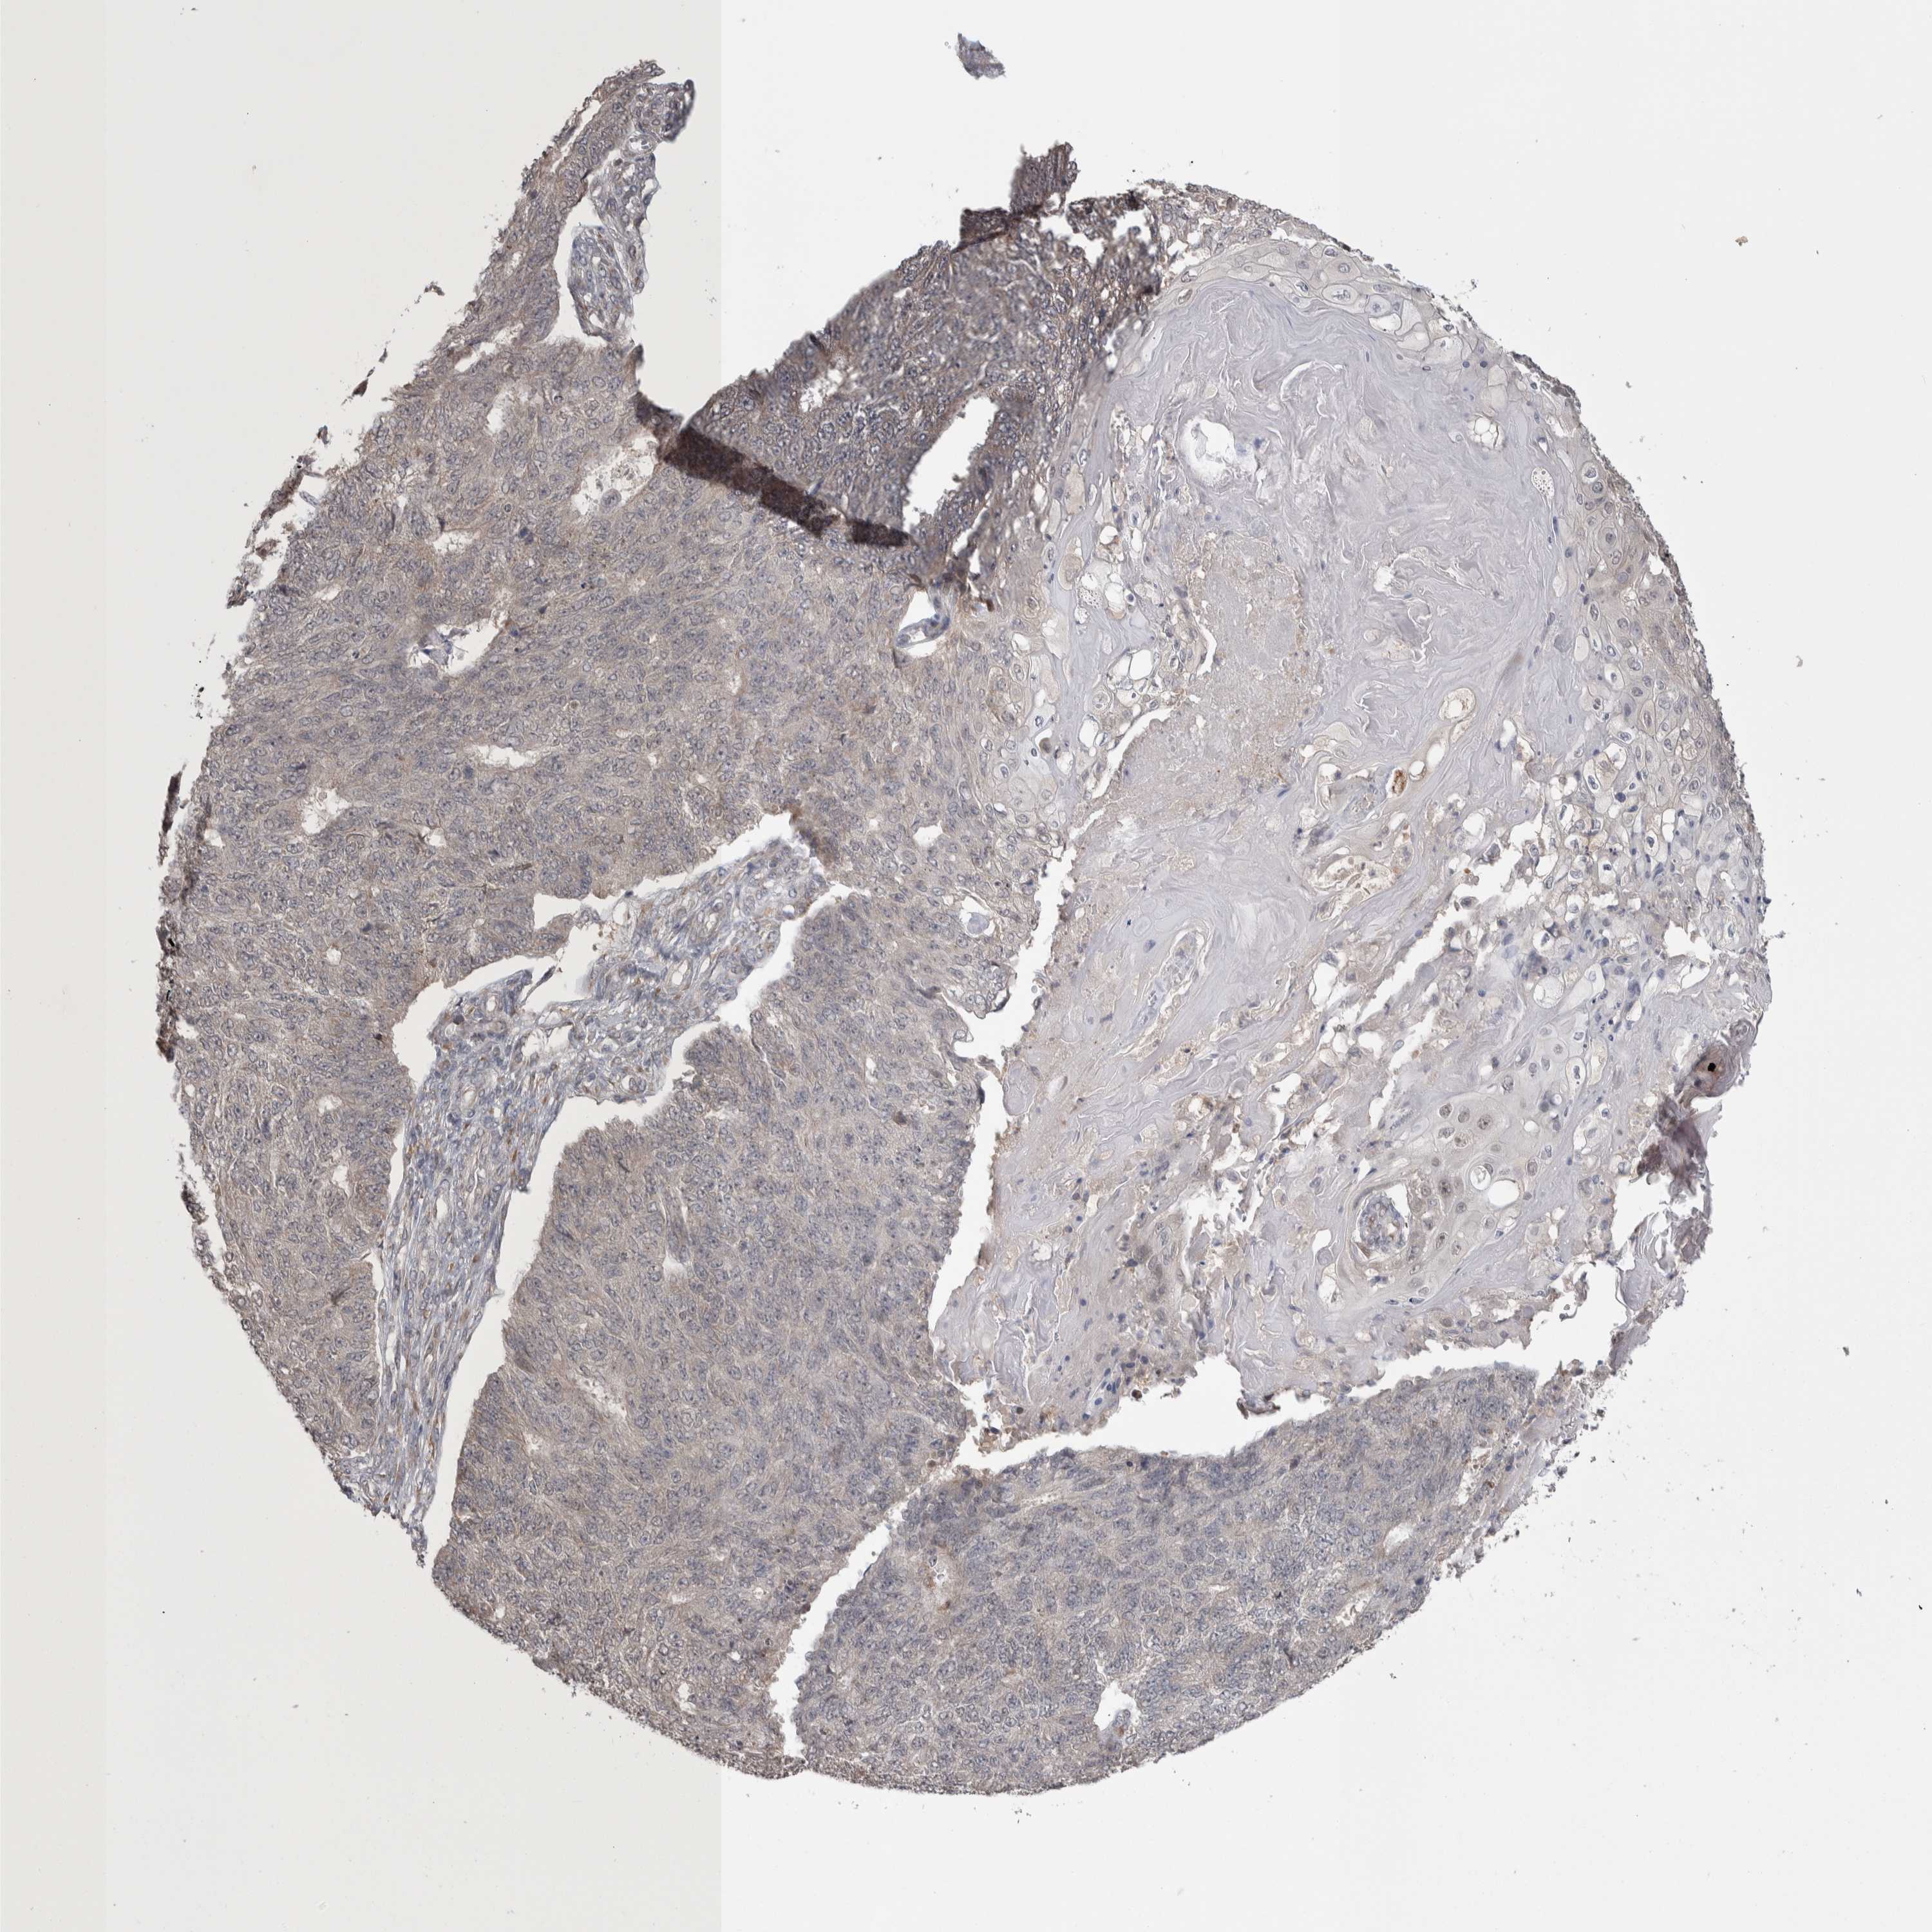

ENDOMETRIAL CANCER - Protein expressioni

A mouse-over function shows sample information and annotation data. Click on an image to view it in a full screen mode. Samples can be filtered based on level of antibody staining by selecting one or several of the following categories: high, medium, low and not detected. The assay and annotation is described here.

Note that samples used for immunohistochemistry by the Human Protein Atlas do not correspond to samples in the TCGA dataset.

Antibody stainingi

Antibody staining in the annotated cell types in the current human tissue is reported as not detected, low, medium, or high, based on conventional immunohistochemistry profiling in selected tissues. This score is based on the combination of the staining intensity and fraction of stained cells.

Each image is clickable and will lead to virtual microscopy that enables deeper exploration of all samples and also displays staining intensity scores, fraction scores and subcellular localization as well as patient and tissue information for each sample.

Antibody HPA024578

Antibody CAB002677

Staining

High

Medium

Low

Not detected

Intensity

Strong

Moderate

Weak

Negative

Quantity

>75%

75%-25%

<25%

None

Location

Nuclear

Cytoplasmic/membranous

Cytoplasmic/membranous,nuclear

Adenocarcinoma, NOS

Adenocarcinoma, metastatic, NOS

Neoplasm, malignant, NOS